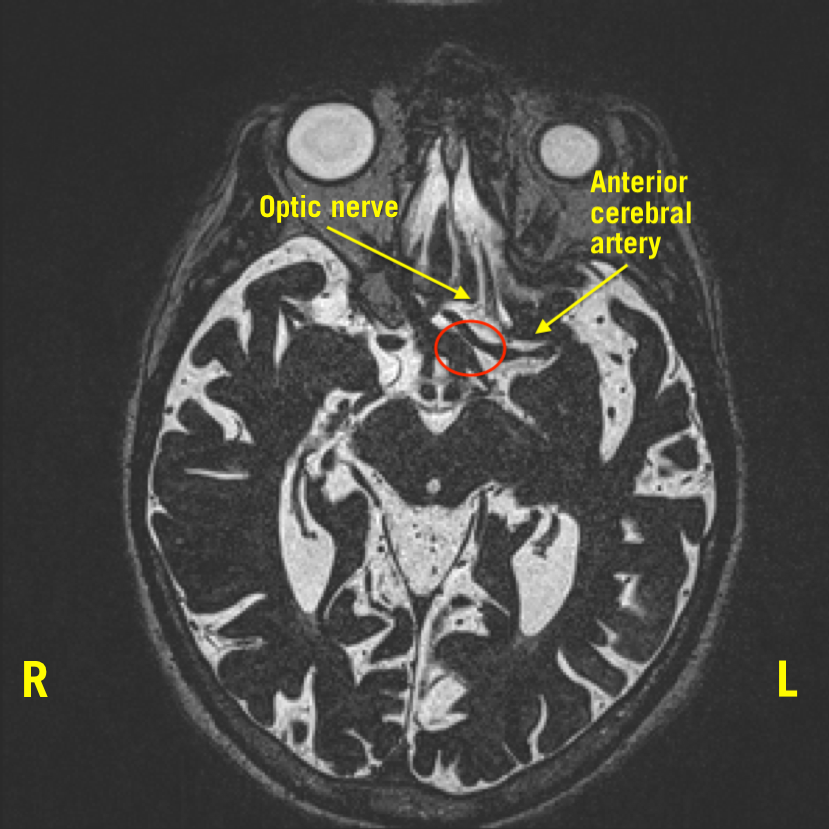

MRI of the orbit was significant for a flattening of the left optic nerve anterior to the optic chiasm, with a prominent flow void from the left anterior cerebral artery (ACA) crossing over the superior aspect of the nerve. Additionally, a mild mass effect was seen inferiorly from the internal carotid artery (ICA), contributing to the compression of the left optic nerve (Figures 1-3).

Figure 1. Thickened left ACA crossing on top of the optic nerve, obliterating its visualization. The red circle notes compression.